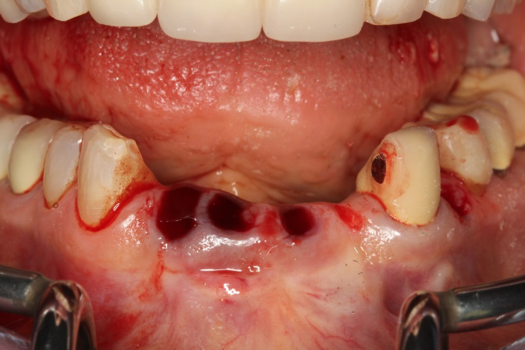

Fig 37. Pontic removal of No. 23 and teeth extractions.

Figure 37

Fig 38. Periodontal casualties.

Figure 38

On the day of surgery, the plan was to extract teeth Nos. 21, 23, 24, 25, and 26, place 3.0 x 13-mm implants in the anterior region due to limited spacing, and place a 4.1 x 10-mm implant in the No. 21 extraction site. Before the extractions were performed, the No. 23 pontic was sectioned from the existing 2-unit cantilevered bridge utilizing ceramic and metal high speed rotary cutting burs ZR 6881 and H34L (Komet-USA), respectively. After removal of the pontic and extractions, the surgical guide was verified to be seating positively (Figure 36 through Figure 38). Surgical guide protocol was followed, and all implants were successfully placed and torqued to a value of greater than 35 Ncm (Figure 39 and Figure 40). All implants were placed without flapping, with the exception of No. 23. The flap was elevated to reposition lingual keratinized tissue facially for enhanced esthetic tissue profile. The implants were then prepared with a high-speed carbide bur (Komet-USA) with copious amounts of water (Figure 41 and Figure 42). The one-piece 3.0-mm diameter implant served the needs of the patient's spacing requirements. Inter-occlusal space requirements and path of draw were verified. The PMMA provisionals were air abraded and relined with crown-and-bridge material (Figure 43 through Figure 45).